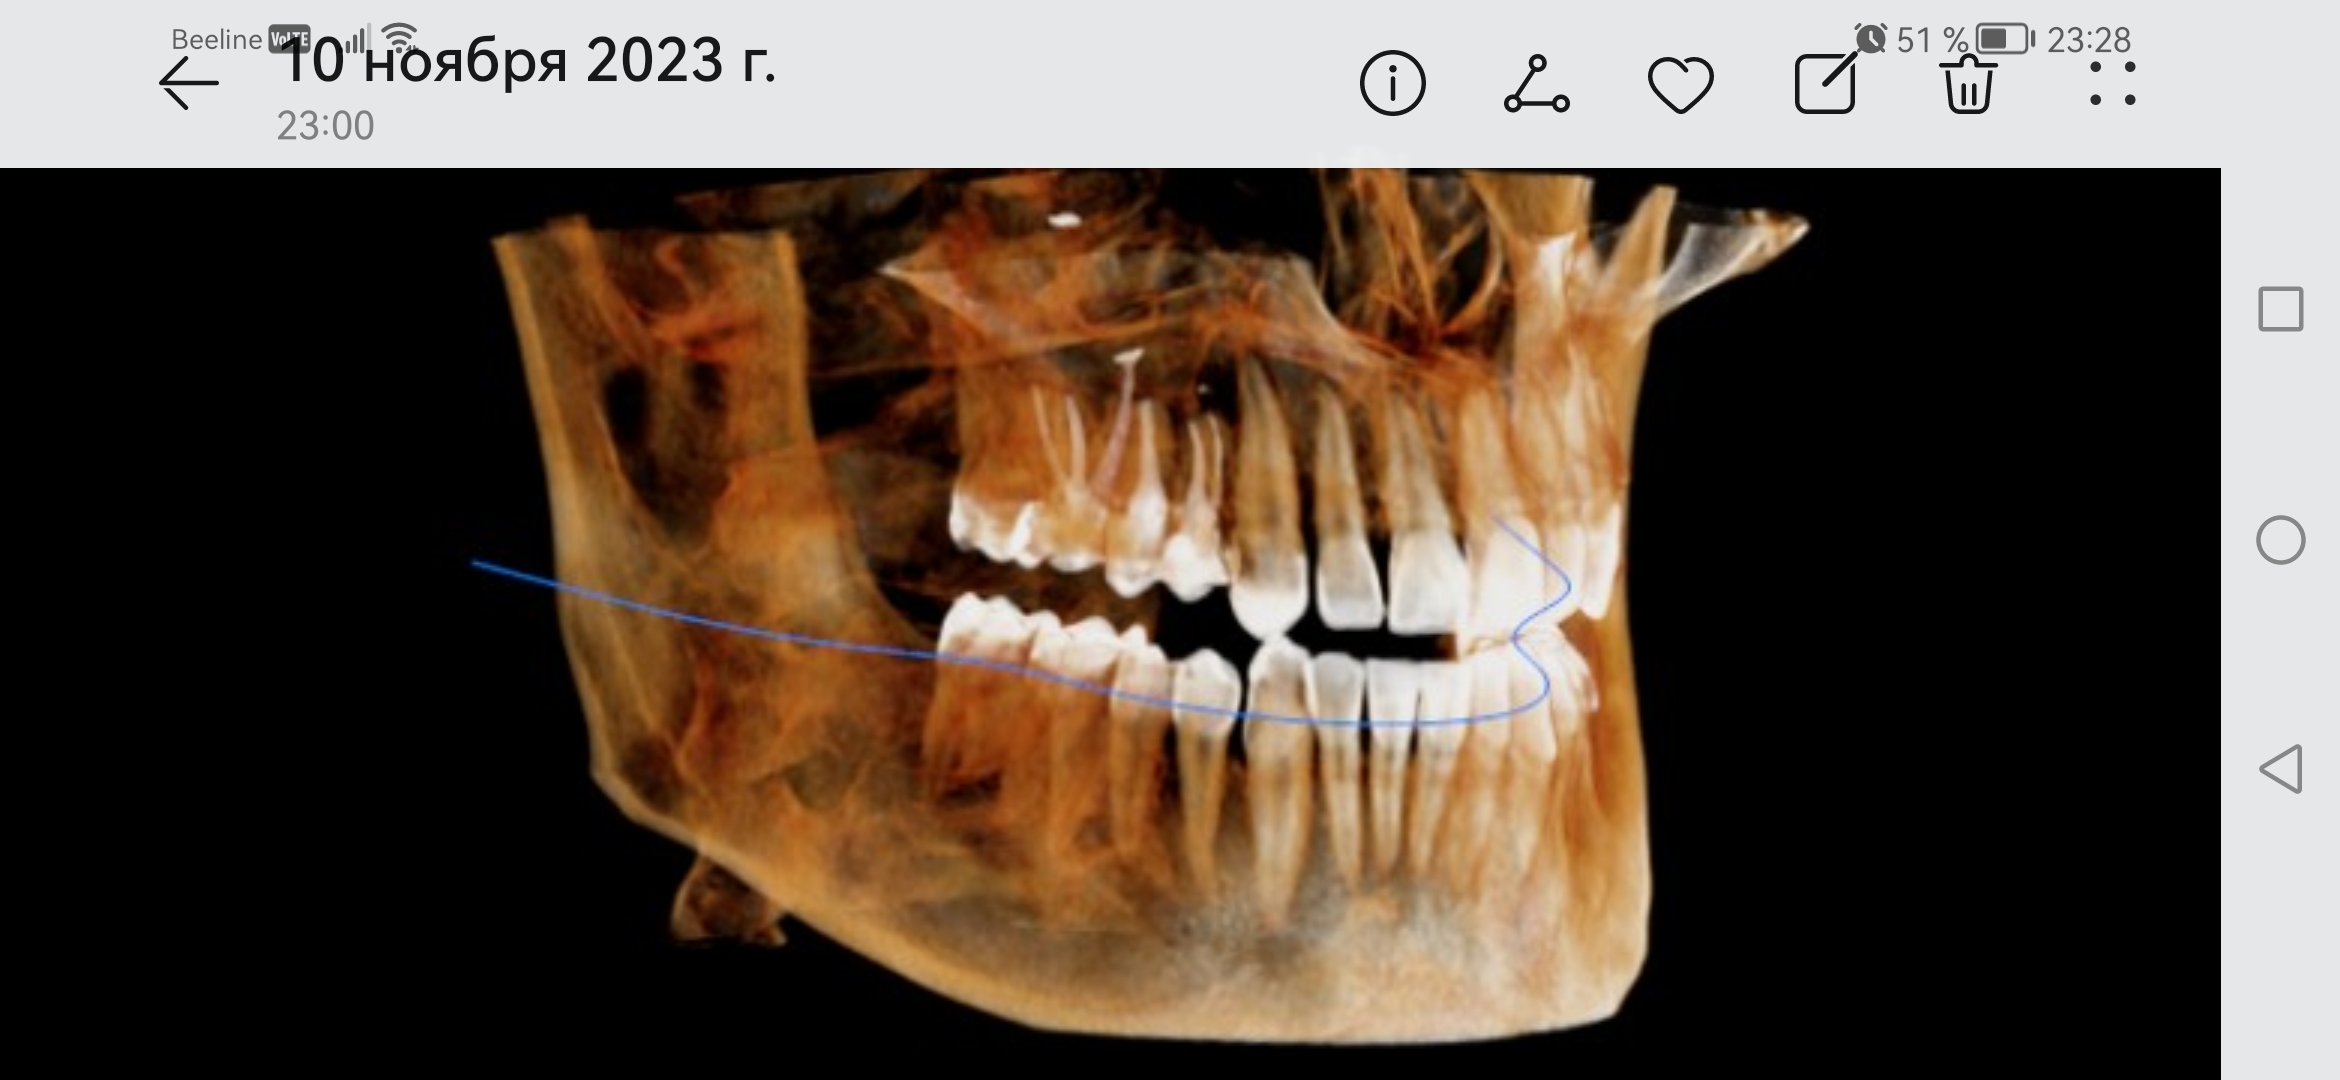

Screenshot20231[...].jpg 414Кб, 2340x1080

2340x1080

Screenshot20231[...].jpg 482Кб, 2340x1080

Боя, я в ахуе, вы в каком веке живёте. Есть такая штука как КЛКТ, стоит копейки, делается 2 минуты. Является золотым стандартном диагностики ЛЮБЫХ зубных пиздецом, там в 3д видно все - кисты, периодонтиты, состояние пазух и тд. Любой приличный врач а) не станет производить серьёзных манипуляций без таких снимков б) спокойно все увидит и распишется где и из за чего у вас болит. Нет бля ходят что-то лечат неизвестно что, не могут определить что и где у них болит, вы ебанутые?